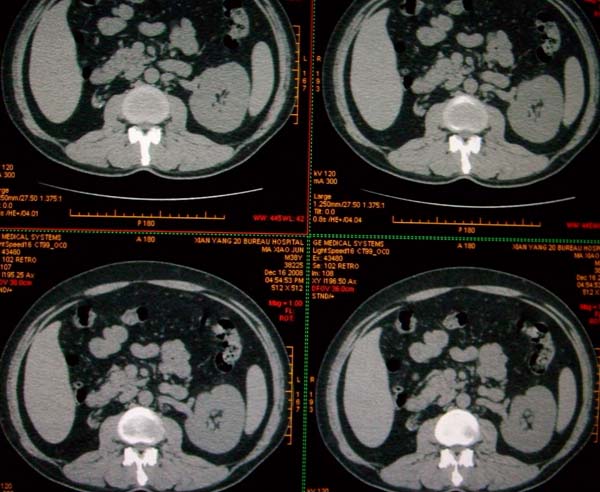

标题: CT17174:M38Y,体检超声提示右肾发育不良,病人无明显不适 [打印本页]

标题: CT17174:M38Y,体检超声提示右肾发育不良,病人无明显不适

右肾发育不良;考虑左肾下极血管平滑肌脂肪瘤可能,建议增强。

右肾微小发育不良  左肾下极错构可能

1)左肾下极占位性病变,不排除肾癌可能;建议行进一步检查。2)右肾发育不良。

左肾下极占位性病变,不排除肾癌可能;建议增强及明确内部组织ct值。右肾发育不良。

右肾发育不良。左肾代偿。左肾下极占位,性质待定,建议强化。

右肾发育不良。左肾下极囊实性占位,建议增强。